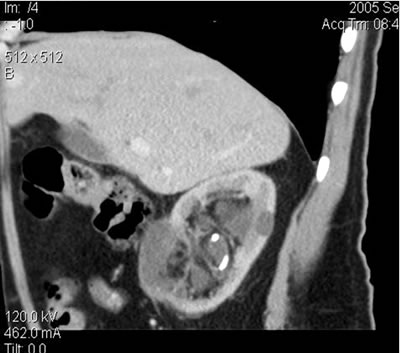

Мониторинг

(10 месяцев) 22 ноября 2005

Спиральная компьютерная томография

(СКТ)

в нижнем сегменте - образование

размером 37х35х27 мм, при болюсном усилении накапление

контрастного вещества (max 21-23 HU)

Спиральная компьютерная

томография (СКТ)